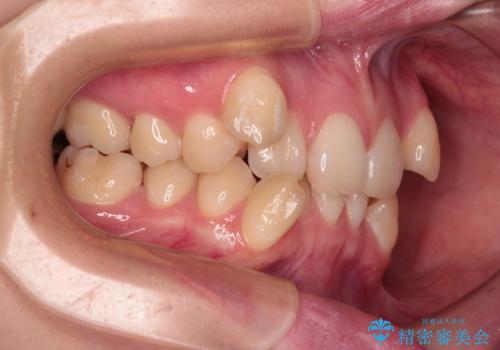

上下の八重歯とクロスバイト ワイヤー装置での抜歯矯正

- 八重歯とクロスバイトを気にして来院された患者様です。

上下ともに八重歯が顕著であり、前歯のクロスバイトがあったため、上下左右の第一小臼歯4本を抜歯し、ワイヤー装置での抜歯矯正を行うこととしました。